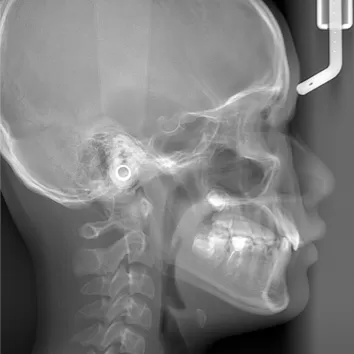

X-rays before treatment

[Panoramic Radiography/Lateral Cephalogram]